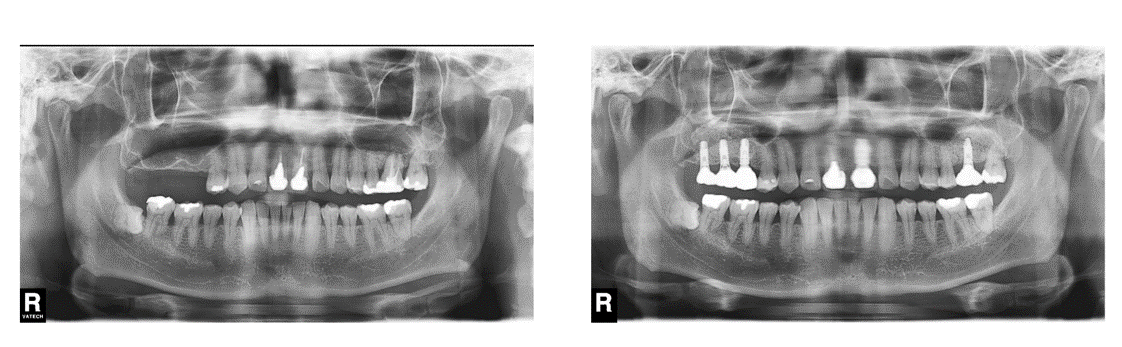

インプラント治療の症例1

(上顎の奥歯と前歯がない)

治療前

治療後

| 診断名・主訴 | ①右上インプラント希望 ②前歯と左上が痛い |

| 年齢 | 45歳 |

| 治療期間 | 2年間 |

| 治療内容 | インプラント治療 |

| 治療に用いた主な材料、設備機器 | 京セラFINESIAインプラント 上部構造:ジルコニアセラミック |

| 抜歯部位 | 左上1・6 |

| 治療費 | 約250万 |

| リスク・副作用 | 術後出血や腫れ |